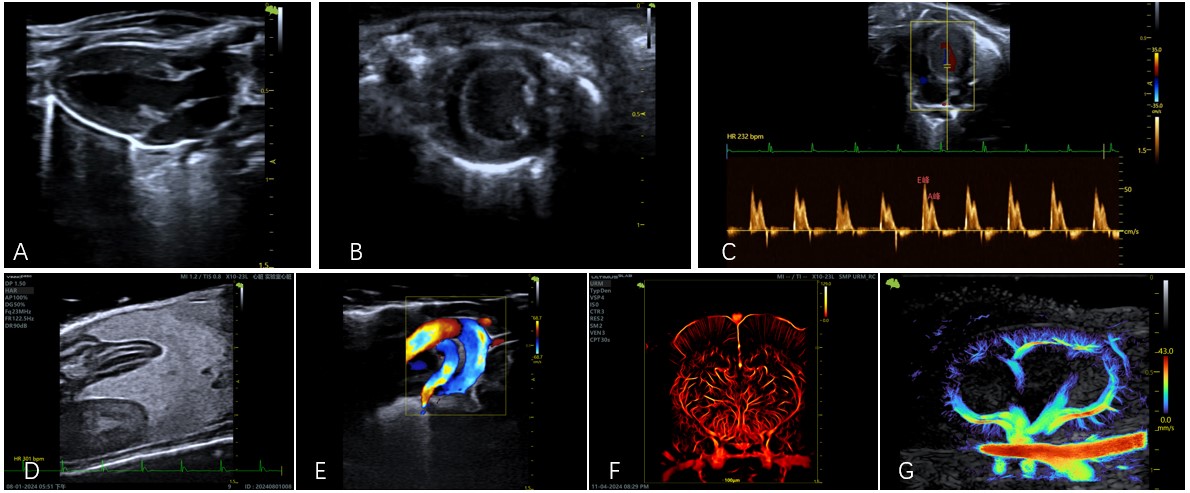

应用实例:心脏结构与功能评估(图A心脏胸骨旁长轴切面、图B胸骨旁短轴切面、图C心尖四腔心切面二尖瓣血流频谱图、图E主动脉弓血流彩色多普勒图)、腹部脏器(图D脂肪肝)、URM超分辨显微血流成像(图F脑部、图G肾脏)

核心功能主要包括:一、B 型(二维)超声通过灰度图像实时显示组织器官的解剖结构与形态,广泛用于心脏疾病模型监测结构变化,腹部脏器(如肝、肾)、生殖系统(子宫、卵巢)及浅表器官(甲状腺)的解剖结构扫查。二、M 型超声以时间 - 深度曲线动态记录组织运动轨迹,主要用于心脏结构与功能评估(如观察左右心室壁搏动、三尖瓣瓣膜运动)等动态追踪。三、CF(彩色多普勒)、PW(脉冲波多普勒)可检测特定深度的血流速度与方向,常用于诊断血管狭窄、流速变化、血流量等血流动力学异常(如判断下肢动脉阻塞),整体可满足解剖结构观察、运动功能评估及血流状态监测等多种科研需求。四、URM超分辨显微血流成像以注射入血管中微泡作为定位手段,通过监测每个微泡运动轨迹,从而得到相应的血管形态和血流动力学参数。可用于脑部的精细血流成像,以及肾脏、肝脏的微血管的血流成像。